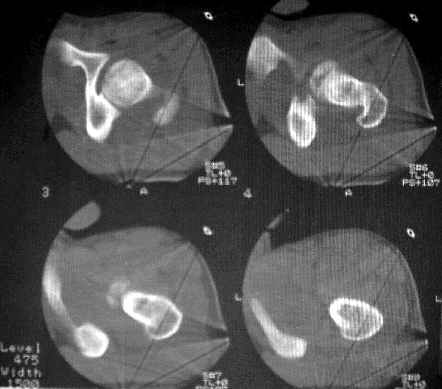

После рентген дообследования складывается мнение об отрыве дистального конца связки головки бедра с костным фрагментом головки (КТ2 скан 3, 4, КТ3 скан 1, прямая проекция - нижнийот 19.05). Данный вариант травмы встречается не часто, но известен, если мне не изменяет память, например см. Мюллер М.Е., Алльговер М., Шнайдер Р., Виллинеггер Х. Руководство по внутреннему остеосинтезу. - Springer-Verlag, 1996. - 750 с. С моей точки зрения, оптимально было бы остеосинтез головки, в обязательном порядке с сохранением целостности связки головки бедра. Как это технически выполнить - вопрос не простой. Кто знает и делал ???

Уважаемые коллеги! Заканчивая обследование больного с переломо-вывихом бедра сделал ему обычные R-томограммы. Кажется удалось "поймать" и отломок и донорское место. Мои выводы - в скиаграмме. Считаю, что это передне-нижний фрагмент головки, образовавшийся вследствии отрывного перелома. На томограммах отломок обозначаю длинной стрелкой, а место откуда он оторвался - более короткой. Учитывая тот факт, что его размеры по КТ 25 х 15 мм считаю, что его фиксация на место необходима для профилактики артроза, что при 16-ти летнем возрасте пациента важно в плане максимального отодвигания эндопротезирования. Планирую оперировать его 24.05.05 г. Результаты представлю.

Несколько соображений к "картинкам". На прямом снимке и КТ-томограммах все типичные линии вертлужной впадины: крыша, передняя стенка, задняя стенка - сохранены. На КТ-сканах 6 и 7 появляется фрагментация головки. С учетом R-томограмм отломок расположен спереди-снизу, а не сзади-сверху от сустава, как написано в описании КТ.